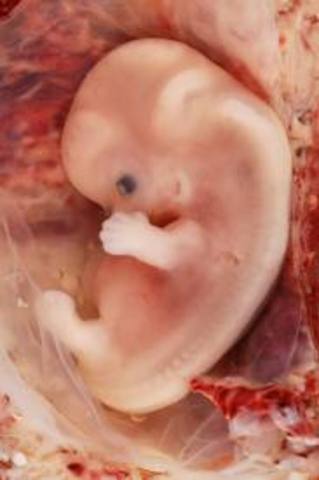

• Week 8

Week 8

The embryo is now around 1.3 cm in length. The rapidly growing spinal cord looks like a tail. The head is disproportionately large